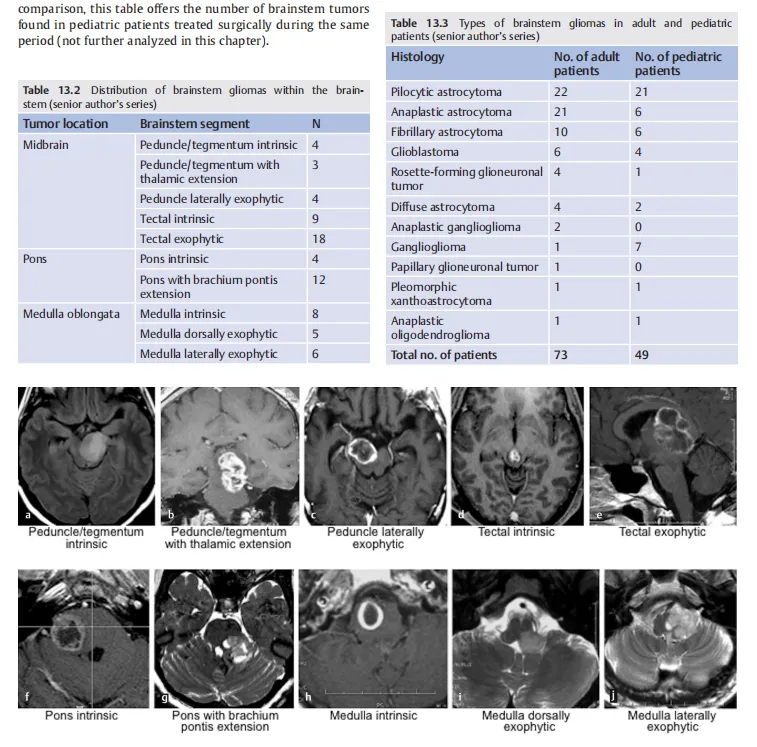

2020年新版的世界脑干手术专著《Surgery of the Brainstem》(脑干手术)中,巴特朗菲教授撰写的《adult brainstem glioma》(成人脑干胶质瘤)这一章节,回顾性研究了1996年至2017年间接受手术治疗的73例患有脑干神经胶质瘤的成年患者。重点详细阐述了脑干手术的技术要点、操作技巧、手术入路、手术体位等,已成为神经外科医生的学习典范。

中脑胶质瘤手术案例

脑桥胶质瘤手术案例

延髓胶质瘤手术案例

在同年出版的世界脑干手术专著《Brainstem Tumors》(脑干肿瘤)中,巴特朗菲教授撰写《Surgical Approaches to Medullary Tumors》(延髓肿瘤的外科手术方法)章节。这本具有启发性和综合性的著作,为读者提供了脑干手术的全面和详细的视角,以及有关病理诊断和治疗管理的先进的讨论。